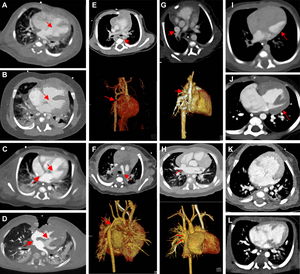

image: Cardiac photon-counting CT (PCCT) in a 174-day-old male infant with complex congenital heart defect. (A) Contrast-enhanced axial PCCT image shows sonographically suspected sinus venosus defect with partial anomalous pulmonary venous connection. (B) Contrast-enhanced coronal PCCT image. (C) Anterior view of three-dimensional reconstruction shows a partial anomalous pulmonary venous connection of two separate lung veins from the right upper and middle lobe to the right superior vena cava (red arrows) and a persisting left superior vena cava (yellow arrow). (D) Three-dimensional reconstruction, posterior view. The diagnosis was confirmed at PCCT, and PCCT allowed for visualization of the partial anomalous pulmonary venous connection of two separate lung veins from the right upper and middle lobe to the right superior vena cava. One lung vein drains correctly to the left atrium (green arrow). A sinus venosus defect, an atrial septum defect, an enlarged right atrium and a persisting left superior vena cava are shown. The only regular confluence of a single right lung vein into the left atrium is shown (D; green arrow). Image quality was rated as 5 of 5 (optimal). view more